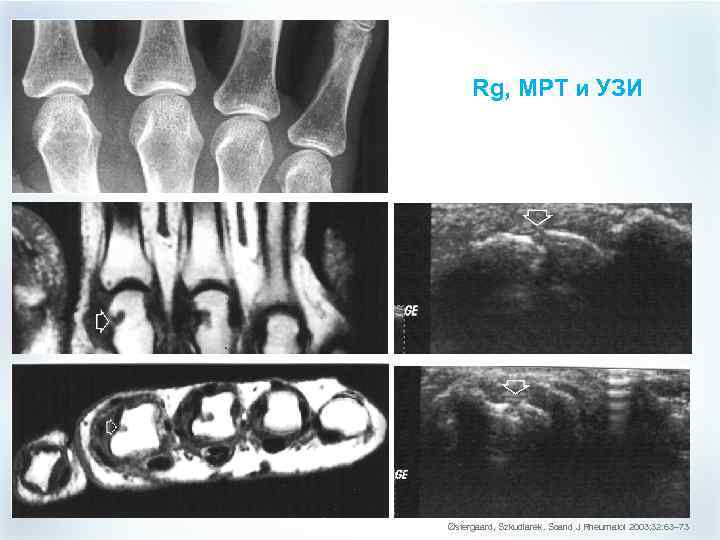

МРТ (в сравнении с Rg): достоинства и недостатки § § Недостатки Больше времени Более дорого Меньше суставов Меньше апробирован M Østergaard, 2006 Достоинства § § § Нет ионизирующей радиации Более чувствителен (эрозии) Много более чувствителен для мягких тканей, включая оценку воспаления суставов (синовита)

МРТ (в сравнении с Rg): достоинства и недостатки § § Недостатки Больше времени Более дорого Меньше суставов Меньше апробирован M Østergaard, 2006 Достоинства § § § Нет ионизирующей радиации Более чувствителен (эрозии) Много более чувствителен для мягких тканей, включая оценку воспаления суставов (синовита)

Rg, МРТ и УЗИ Østergaard, Szkudlarek. Scand J Rheumatol 2003; 32: 63– 73

Rg, МРТ и УЗИ Østergaard, Szkudlarek. Scand J Rheumatol 2003; 32: 63– 73

МРТ и Rg: данные исследований 78% новых эрозий были выявлены при МРТ на 1 или более лет раньше (медиана 2 года) M Østergaard, 2006

МРТ и Rg: данные исследований 78% новых эрозий были выявлены при МРТ на 1 или более лет раньше (медиана 2 года) M Østergaard, 2006